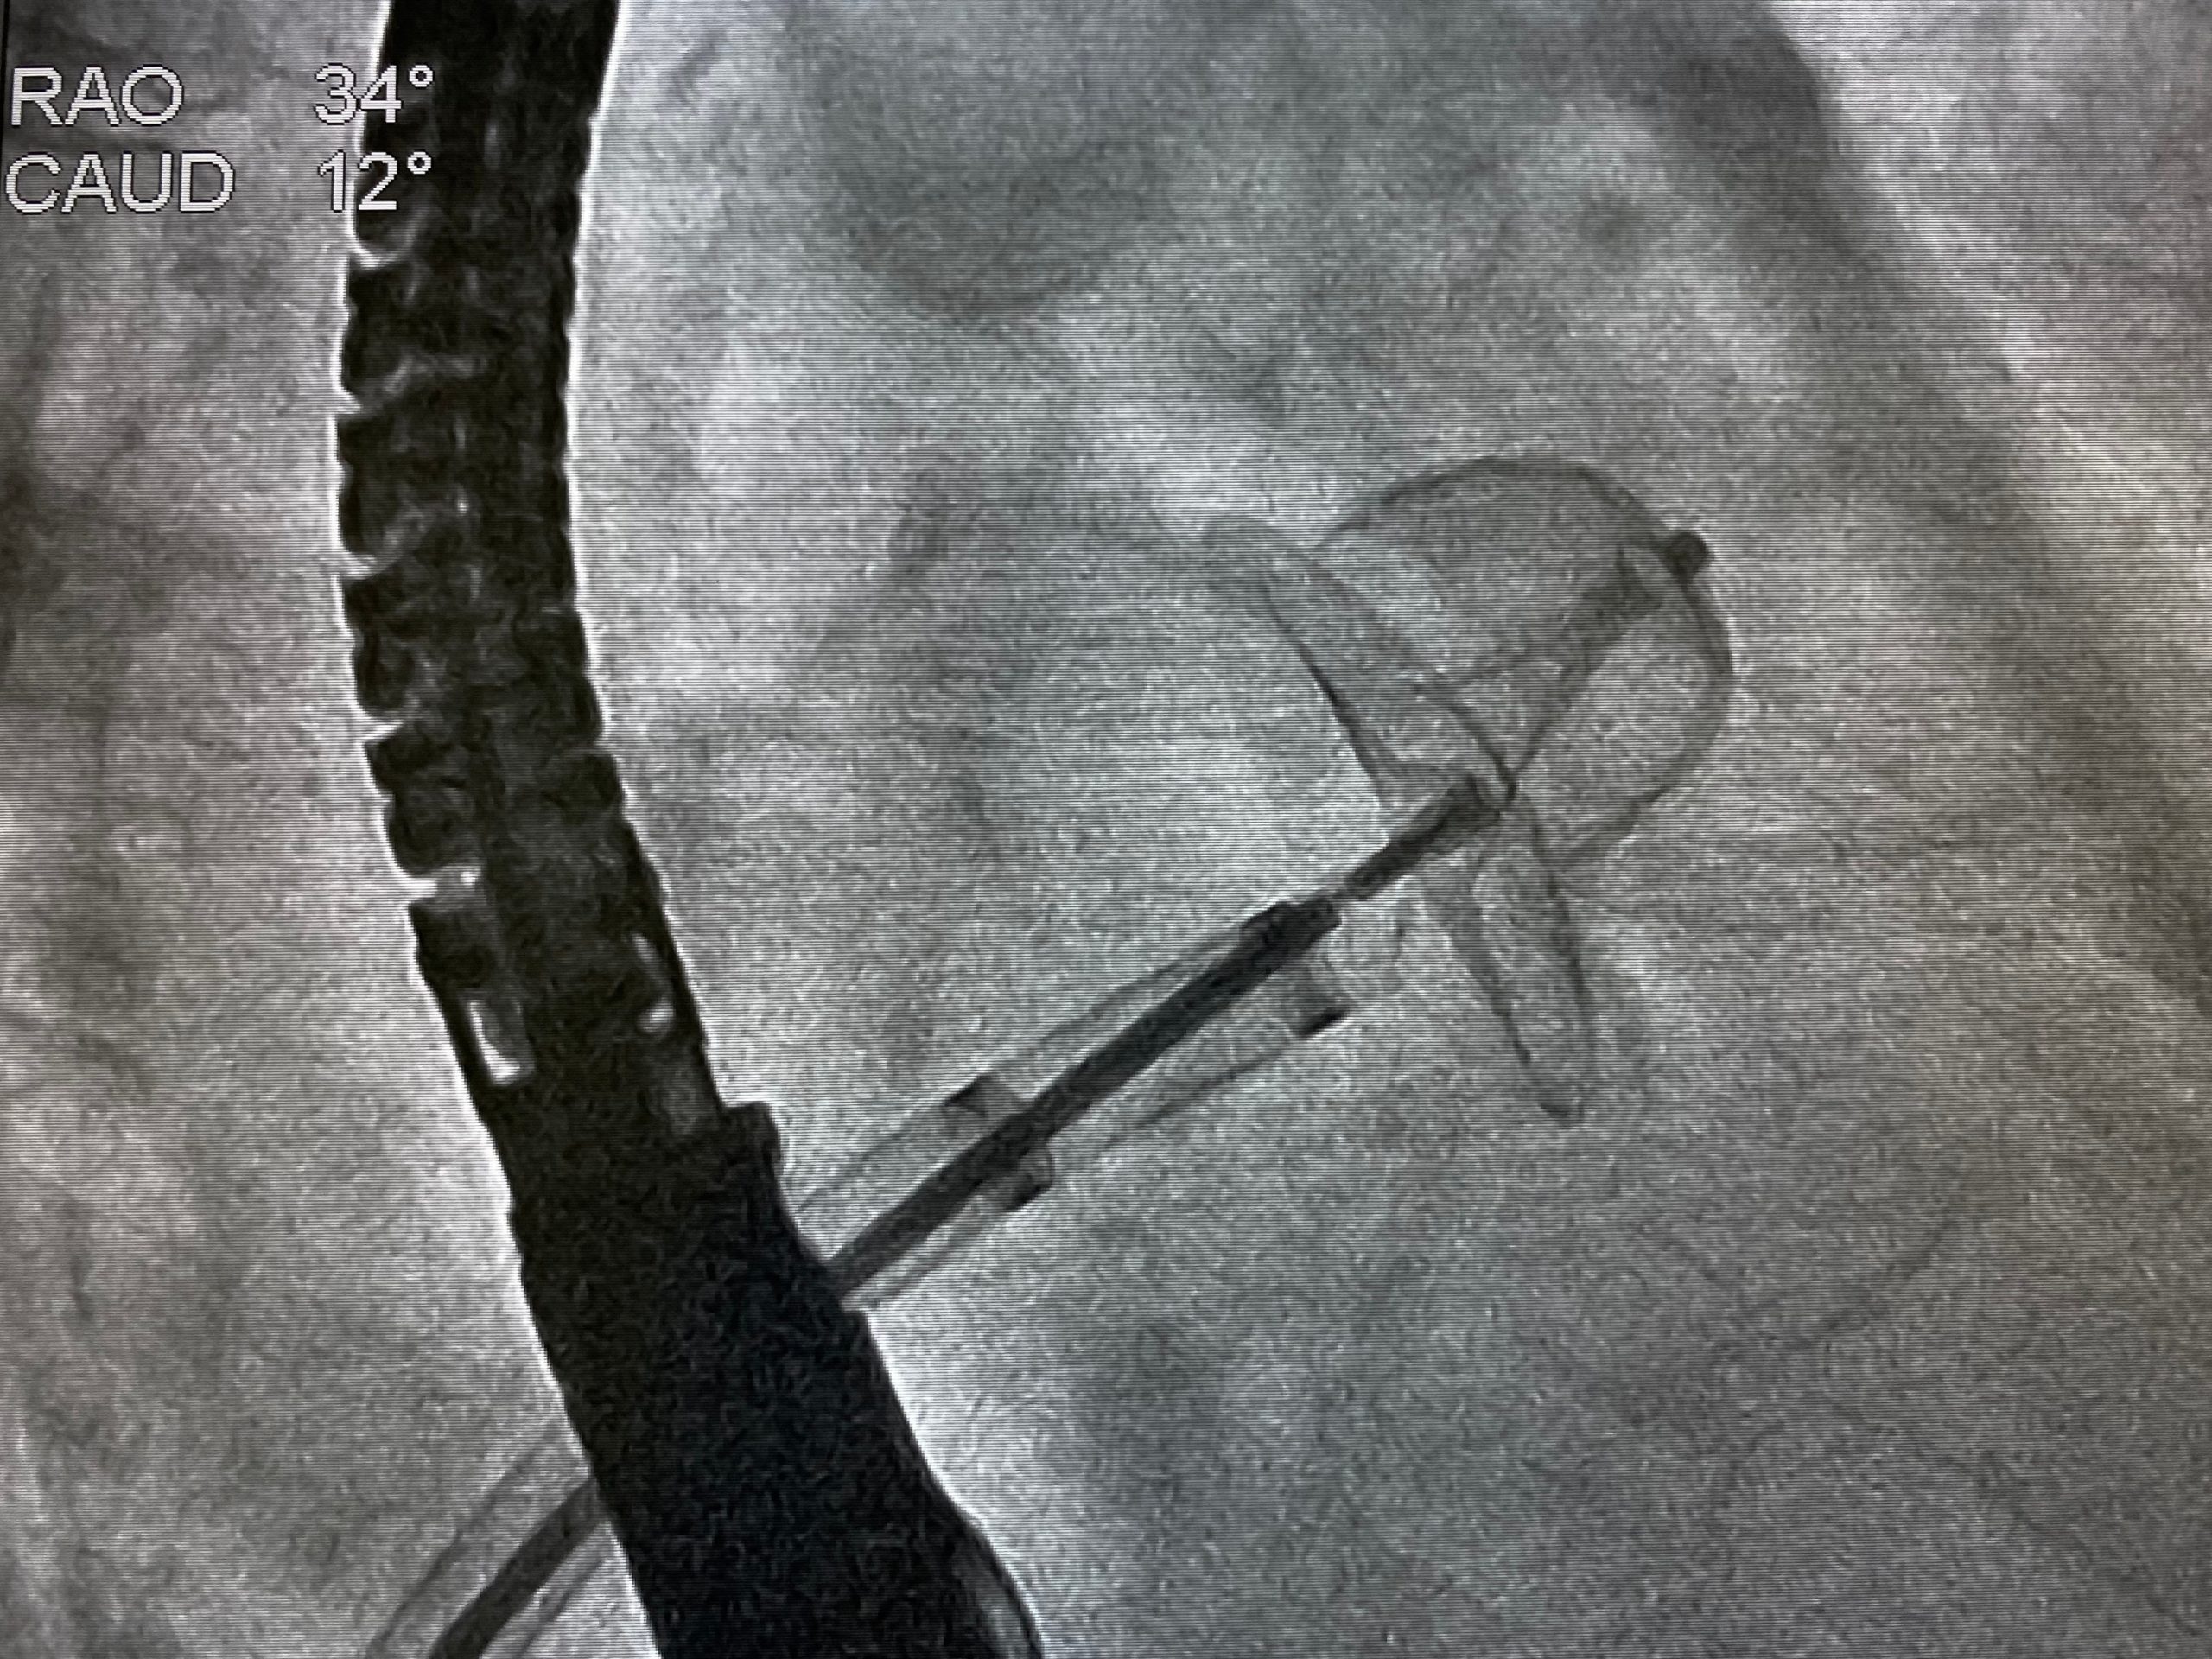

left atrial appendage closure

According to Mostafa Reda Mostafa and collaborating researchers, left atrial (LA) appendage closure (AC) showed an ...

In a meta-analysis published in the Anatolian Journal of Cardiology, researchers assessed the effectiveness of catheter ...

According to a study published in Cardiovascular Intervention and Therapeutics, the safety and efficacy profiles of left ...